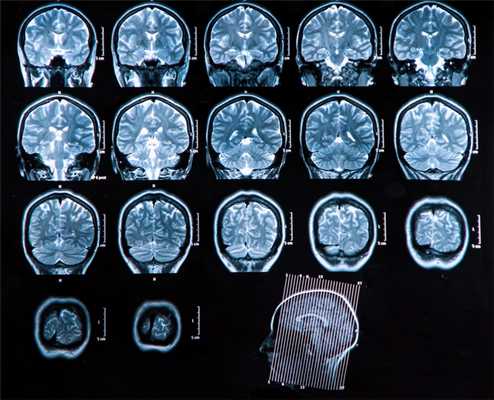

Головной мозг

Основной метод оценки непосредственно вещества головного мозга (в том числе первичных опухолей и метастазов) — МРТ с применением контрастного усиления.

Вопросы стадирования (поиск отдаленных метастазов) лучше всего решаются с помощью ПЭТ, в том числе с метионином.

Компьютерная томография используется как дополнительный метод в случае, если требуется оценка состояния костных структур, а также при наличии абсолютных противопоказаний к МРТ исследованию (наличие металла в теле — например, кардиостимулятора, ферромагнитных инородных металлических соединений: пластины, протезы, импланты и т.п.)